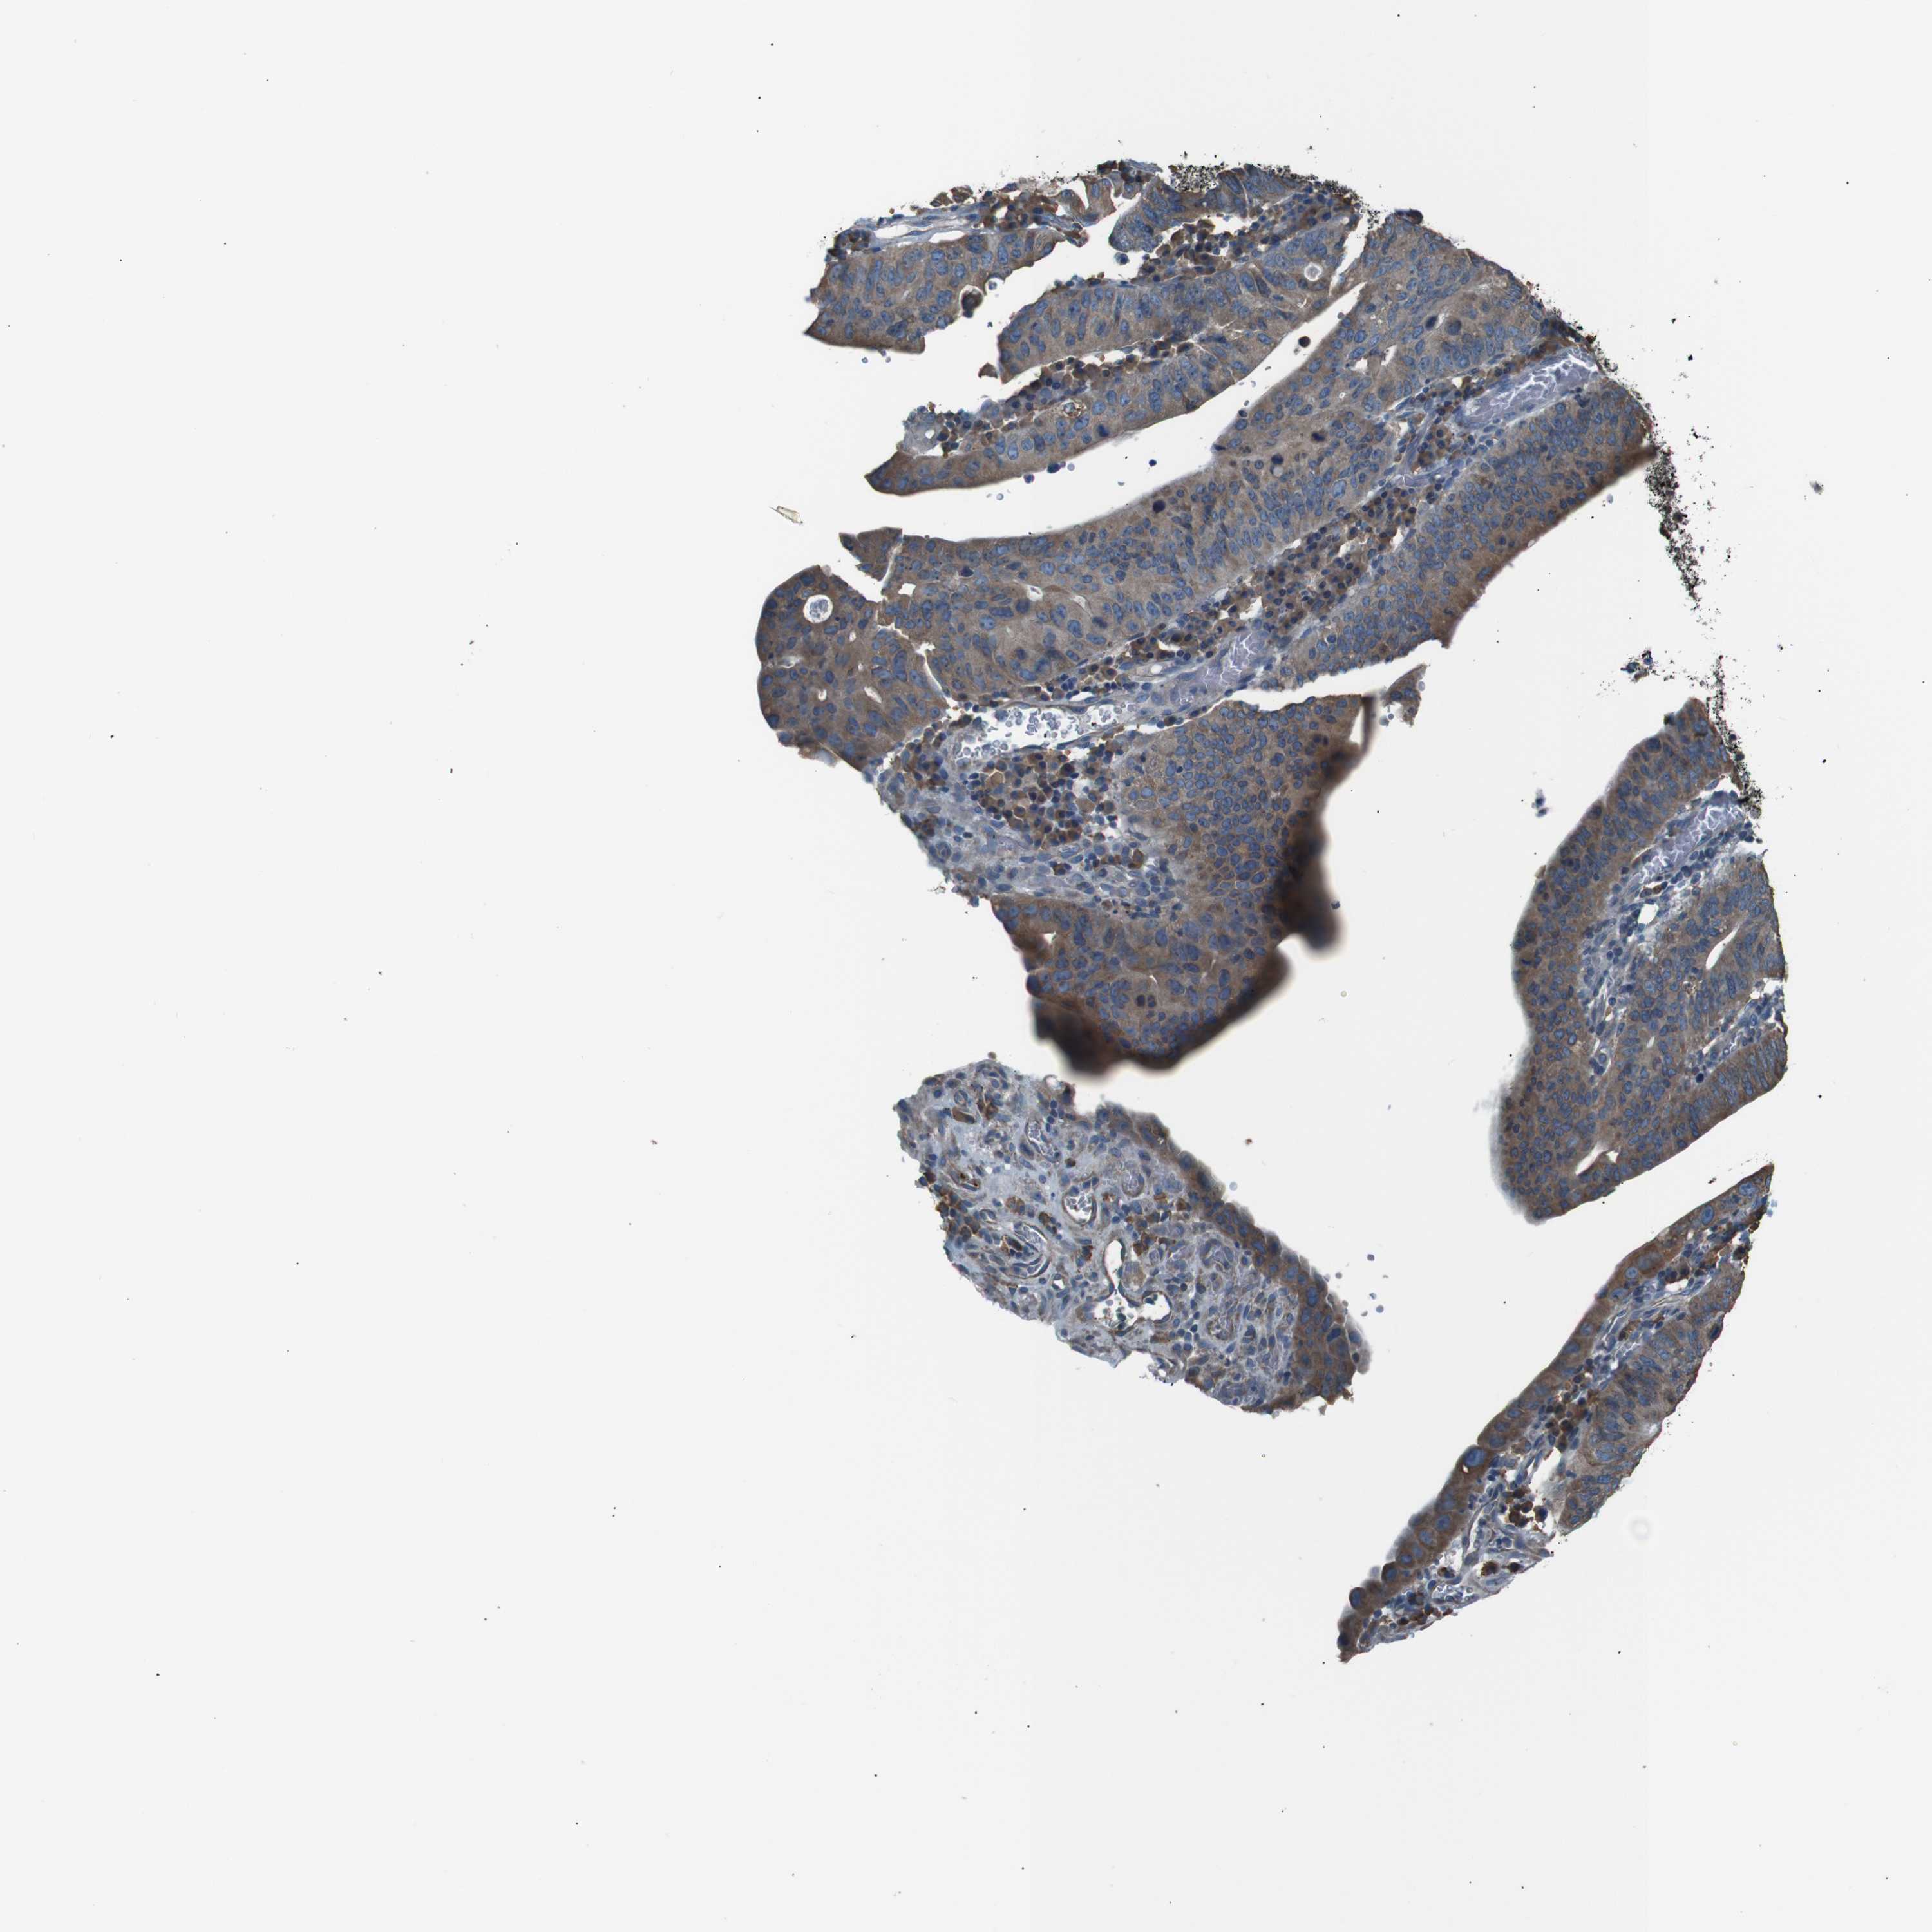

STOMACH CANCER - Protein expressioni

A mouse-over function shows sample information and annotation data. Click on an image to view it in a full screen mode. Samples can be filtered based on level of antibody staining by selecting one or several of the following categories: high, medium, low and not detected. The assay and annotation is described here.

Note that samples used for immunohistochemistry by the Human Protein Atlas do not correspond to samples in the TCGA dataset.

Antibody stainingi

Antibody staining in the annotated cell types in the current human tissue is reported as not detected, low, medium, or high, based on conventional immunohistochemistry profiling in selected tissues. This score is based on the combination of the staining intensity and fraction of stained cells.

Each image is clickable and will lead to virtual microscopy that enables deeper exploration of all samples and also displays staining intensity scores, fraction scores and subcellular localization as well as patient and tissue information for each sample.

Antibody HPA018002

Antibody HPA024071

Antibody CAB013470

Staining

High

Medium

Low

Not detected

Intensity

Strong

Moderate

Weak

Negative

Quantity

>75%

75%-25%

<25%

None

Location

Nuclear

Cytoplasmic/membranous

Cytoplasmic/membranous,nuclear

Adenocarcinoma, NOS

Adenocarcinoma, High grade